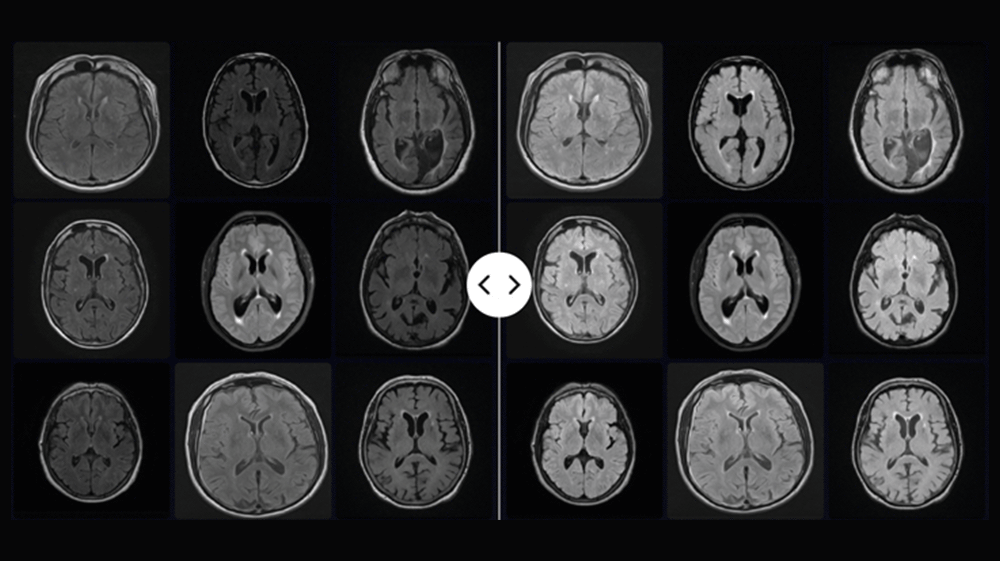

Image harmonization preprocessing for multi-site reproducibility

Ensure high-quality, standardized insights from medical images across sites and scanners with advanced harmonization

We often encounter variability in real-world imaging data due to differences in acquisition protocols and scanner types, leading to significant shifts in image intensity. These inconsistencies hinder traditional interpretation, reduce AI model robustness, and compromise the reproducibility of imaging biomarkers—particularly in MRI.

Harmonization is a critical pre-processing step to enhance AI model generalizability and ensure reproducibility in large-scale studies.

Quibim’s harmonization pipeline standardizes images across scanners and protocols, ensuring consistency and improving AI reliability in multi-site clinical trials.

Dataset of MRI images pre- (left) and post-harmonization (right)